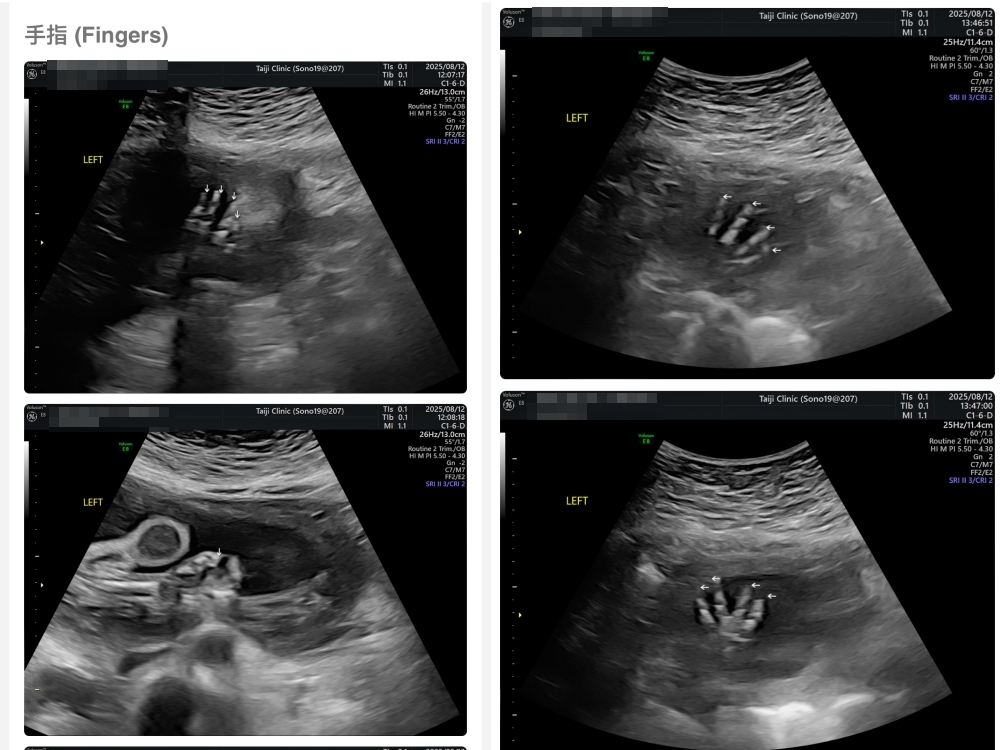

▲離開診所後會收到MAIL,我們14:05離開,大約是16:45收到mail,裡面會有滿滿的超音波照片,紀錄的很詳細!也會提供紙本的報告,可以給日後產檢的醫師做參考👌